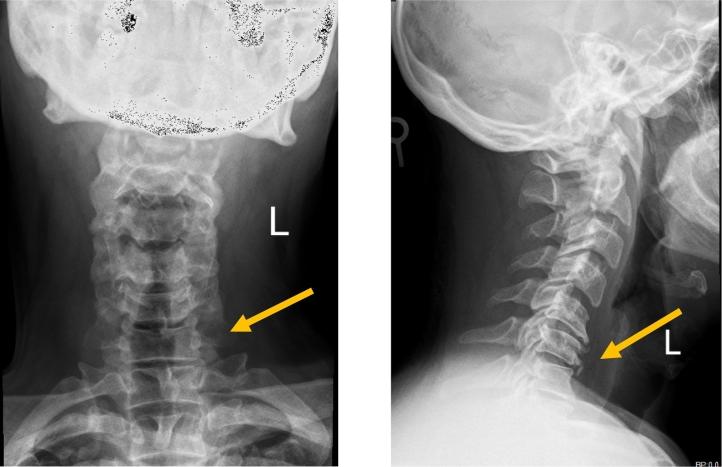

CASE PRESENTATION

A 55-year-old male presenting with neck pain, right and left arms radicular pain and numbness, and unilateral right foot drop following cervical disc prolapse. The patient presented with upper motor neuron lesion signs. MRI showed cervical disc prolapse at two levels, confirming central cause of foot drop. The patient underwent anterior cervical decompression and fusion surgery.

病例报告

一名55岁男性,因颈椎间盘突出症出现颈部疼痛、双侧手臂放射性疼痛和麻木,以及单侧右足下垂。患者表现出上运动神经元损伤体征。磁共振成像显示两个节段的颈椎间盘突出,证实了足下垂的中枢性病因。该患者接受了颈椎前路减压融合手术。